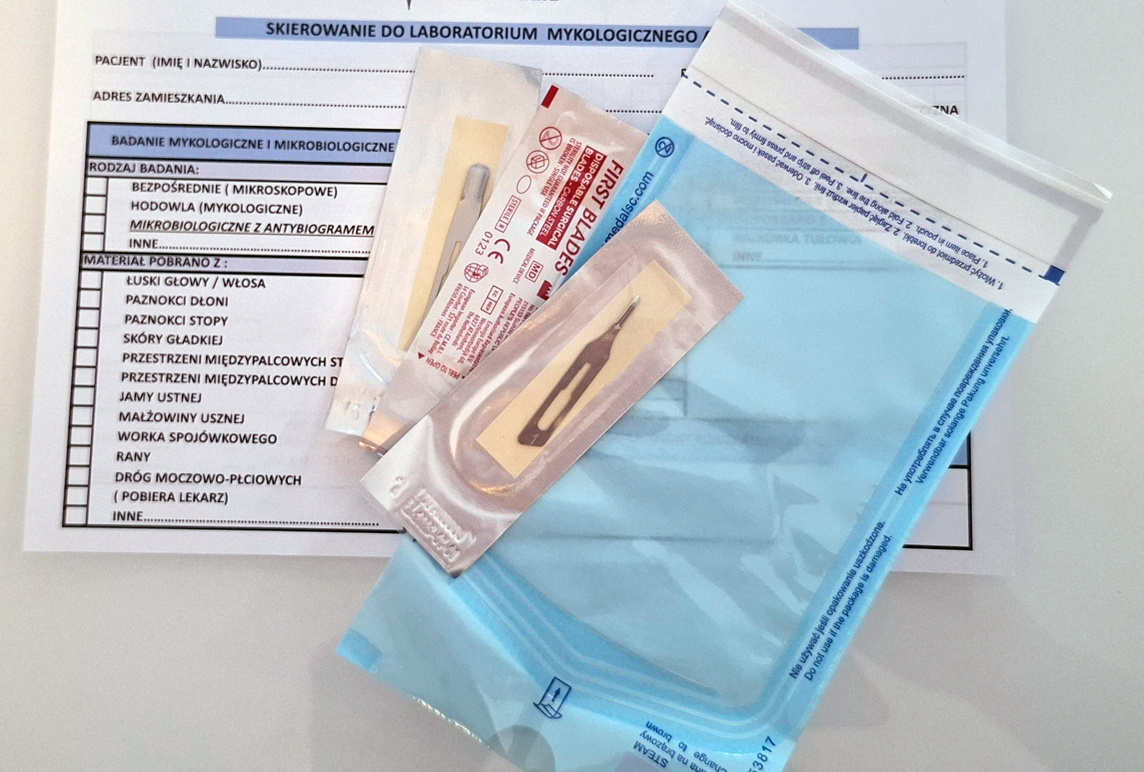

Pobieranie materiału mykologicznego

Pobieranie materiału do badania z paznokci zmienionych, z podejrzeniem nadkażenia grzybiczego. Zabieg jest bezbolesny i pozwala nam na określenie ewentualnego rodzaju patogenu. Ma to znaczenie w doborze metody leczenia. Czas oczekiwania na wynik to około 6 tygodni. Pamiętaj, że samodzielne obcięcie i oddanie paznokcia do laboratorium to nieprawidłowa metoda pobrania materiału, a wynik może wyjść fałszywie ujemny. Zaufaj osobie, która przeszła szkolenie z pobieraniu materiału do badania mykologicznego.

Jak przygotować się do pobrania materiału mykologicznego?

Należy odstawić stosowanie preparatów:

– zewnętrznych (aptecznych i kosmetycznych np.: olejki eteryczne) 6 – 8 tygodni,

– doustne antymikotyki 10 – 12 tygodni,

– lakiery i stylizacja paznokci przynajmniej 6 tygodni,

– dezodoranty, kremy, pudry – 7 dni przed,

– w wieczór poprzedzający badanie należy umyć stopy wodą z mydłem,

– w dniu pobrania próbki nie myjemy stóp.